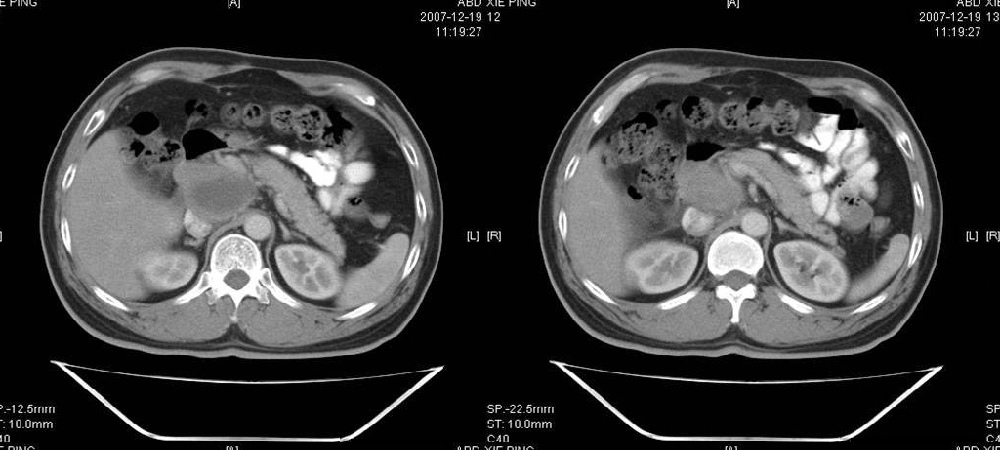

临床病史:患者,男,53岁,因反复上腹部饱胀不适2+月,在餐后或饥饿时明显,伴呃逆,无呕吐、呕血,无腹痛腹泻;2年前腹腔镜胆囊切除,否认肝炎、结核等病史。

pmrc显示病变与12指肠关系密切,与胆系不相通。

考虑十二指肠憩室。从影像上看,病变位于下腔静脉前胰头后方十二指肠内侧,肝尾叶受压,说明病变来源于后腹膜;胰胆管成像胰管和胆道未见扩张,总胆管中段受压未显示,上下段正常,所以不考虑来源与于肝尾叶和总胆管的囊肿。考虑为十二指肠憩室或小网膜囊肿。

楼上高手,本例的确是一例十二指肠憩室.

为什么口服的对比剂没有少量进入憩室里呢?我前段诊断过类似病例,对比剂少量进入憩室内,此病例是否口服对比剂时间短呢?